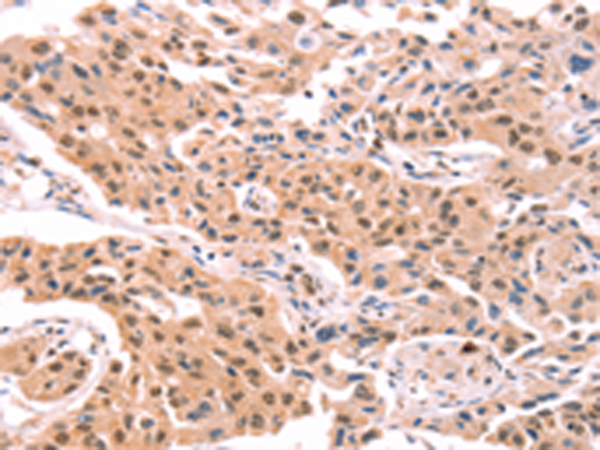

分类: 科研抗体货号: P07714别名: PSA; PROS; PS21; PS22; PS23; PS24; PS25; THPH5; THPH6应用: IHC反应种属: Human